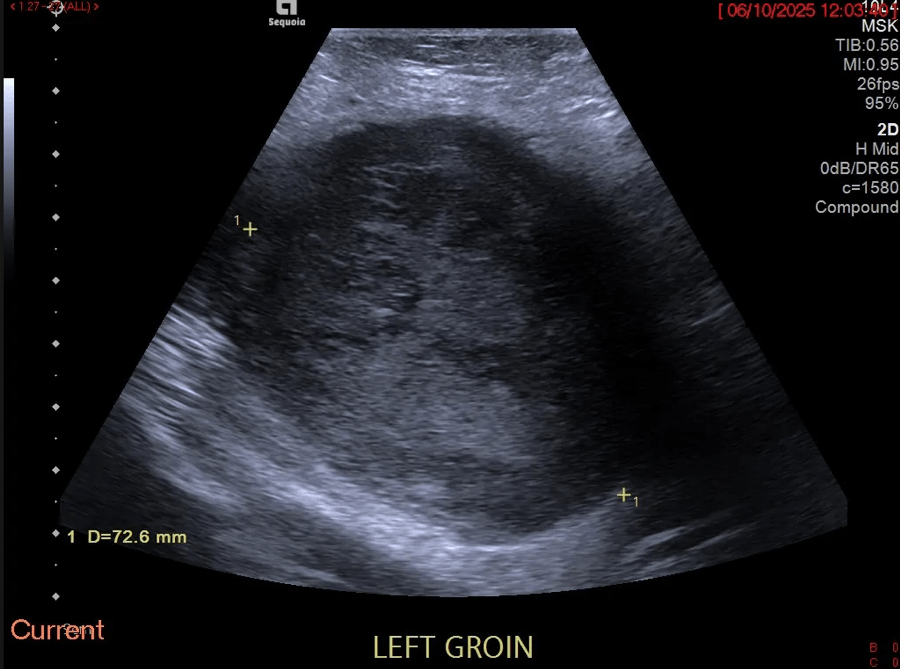

Fig.02. Transverse power Doppler extended field of view imaging shows marked peripheral and intra-lesional vascularity.

Lesion appearances, such as MFS, can be challenging. Ultrasound is a useful adjunct in assessment and differentiation of consistency, vascularity and compressibility. An ultrasound was performed using multi-frequency probes with M-mode and Doppler. The US demonstrated a 7.2cm heterogeneous vascular primary soft tissue tumour rather than an abnormal infiltrated lymph node (Figure 1-3).

Disorganised vascular patterns with abnormal morphology and flow characteristics are recognised as markers of malignancy. The US alone may underestimate deep extension or infiltrative margins, such as in MFS.

Learning Point 2: A comprehensive ultrasound assessment, combined with a focused clinical history and examination at the time of sonographic assessment, is essential in the initial assessment of complex soft tissue lesions. This is supported by the 2024 BMUS assessment of soft tissue lesion guidelines. Suspicious features of malignant soft tissue lesions, such as MFS, including rapid growth, marked intra-lesion vascularity, and a heterogeneous echotexture, were demonstrated in this case. They should prompt further investigation and onward referral.